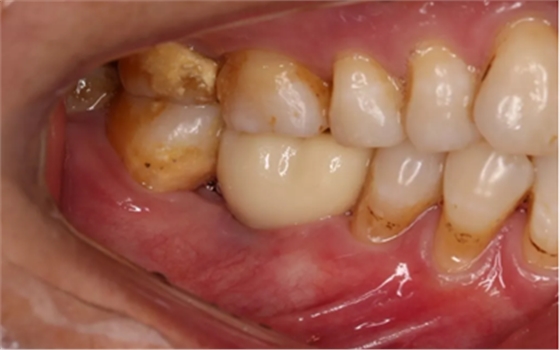

2、术前口腔内照片

46牙烤瓷冠修复,牙周红肿,叩痛,松2度。骨吸收波及邻牙,邻牙牙周情况不佳,45牙松2度,47牙松1度。

(摄于2016年8月31日,反光板协助拍摄)